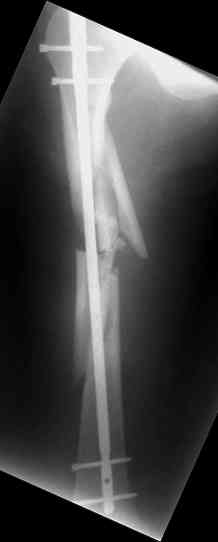

молодй человек 26лет получил С3-перелом правого бедра и легкую черепно мозговую травму (сотрясение головного мозга). Через неделю (противошоковые мереприятия и скелетное вытяжение выполнялось в ЦРБ)оперирован: БИОС бедра стержнем СнМ, Польша. Выписан со швами на амбулаторное лечение по месту жительства в г. Ижевск.Через 1месяц главным врачом больницы, со слов пациента, предложен реостеосинтез пластиной "соберем кость".

Надеюсь сейчас показать перелом, а потом синтез.

Про "кролика", конечно, не очень хорошо с точки зрения деонтологии. Но коллега, Вы думаете кто-нибудь из заядлых Nailer- ов оценит положительно этот остеосинтез? Возможно, на то были объективные причины: отсутствие штифтов большего диаметра..., штифтов, позволяющих блокировать более толстыми винтами..? А уж Plater-ы, конечено засмеют.

У данного пациента есть все основания ожидать несращения. Менять штифт (безусловно тонкий и недостаточно стабильный для этого перелома) на пластину не лучший вариант, особенно, если предполагается открытая операция. Или главный врач в Ижевске имеет ввиду длинную мостовидную пластину LCP по технике MIPO? Тогда шансов на сращение будет больше, чем сейчас, но с нагрузкой придется очень и очень подождать.

Мы бы сейчас перештифтовали : удалить, рассверлить, и забить штифт 13-16 мм диаметром и на пару см. подлиннее. Предпочтительнее штифт, имеющий изгиб во фронтальной плоскости в проксимальном отделе для введения через верхушку б\вертела и имеюший возможность проксимального блокирования по оси шейки бедра.

Не вижу больших оснований для пессимизма, тут все шансы на сращение есть - сделано закрыто, винтики в гвозде есть. С нагрузкой на ногу торопиться не надо только.

По моему мнению не стоит торопиться с реостеосинтезом. Через 6-8 месяцев будет видно консолидацию.

Через 3-4 месяца рекомендую начинать приступать на ногу с нагрузкой 50-80%.